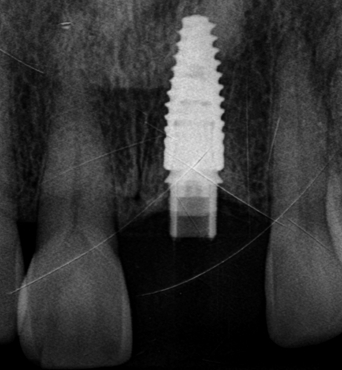

정밀 진단 및 모의 시술

구강 스캔 · CT · X-RAY로

뼈와 신경 위치를 확인

당일 완성된 구강 내 모습

01임플란트2023.06.02 - 2025.03.26

BeforeAfter